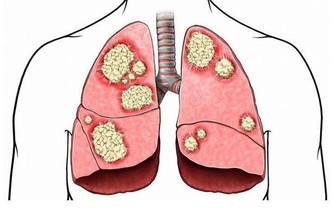

腎虛會導致人體的免疫能力降低,加速衰老,

腎臟一旦出現問題,那麼身體的各種疾病便會隨之而來。

他包括泌尿系統、生殖系統、內分泌代謝系統、神經精神系統及消化、血液、呼吸等諸多系統的相關疾病。